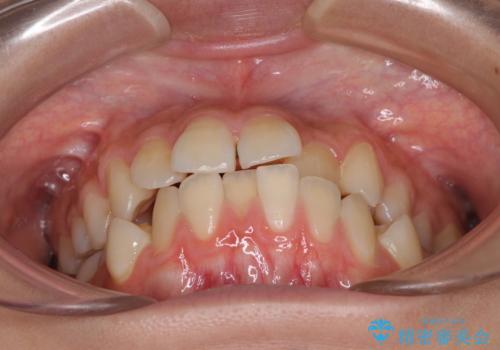

- 下顎の前突感と前歯の叢生を気にして来院された患者様です。

下顎前方位の骨格のため、下顎歯列に対して上顎歯列の幅が狭くなっていました。

上顎骨を拡大しない場合には、奥歯に咬みにくさが残ったり、下顎前歯の歯肉退縮や口元の突出感などが出たりと、妥協的な仕上がりとなります。